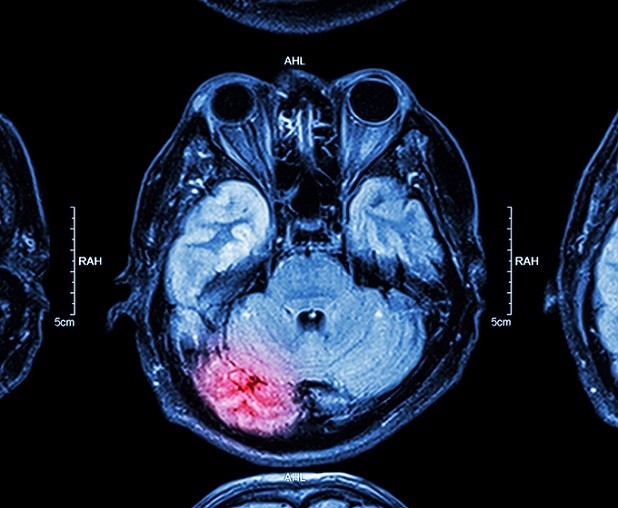

نوروسافاری | تشنج های صرعی در یک نفر از هر ۱۰ نفر که آسیب ترومای مغزی (TBI) را تجربه کرده باشند، اتفاق می افتد. با این حال تحقیقات جدید در دانشگاه تگزاس در سن آنتونیو (UTSA) یک رویکرد نوآورانه برای کند کردن احتمالی پیشرفت صرع را کشف کرده است. محققان در UTSA موفق به حذف نورون های جدید ایجاد شده پس از آسیب مغزی شده اند تا تشنج را کاهش دهند. آنها معتقدند که این تکنیک میتواند بطور بالقوه صرع پس از تروما را کاهش دهد.

به گزارش نوروسافاری از دانشگاه تگزاس، افرادی که آسیب ترومای مغزی را در نتیجه شلیک اسلحه یا تصادفات اتومبیل تجربه کرده اند، در معرض خطر بالای ابتلا به تشنج هستند. در طول تشنج، اختلالات الکتریکی غیر طبیعی ناگهانی در مغز وجود دارد که منتج به علائم مختلفی نظیر حرکت عجیب در سر، بدن، بازوها، پاها یا چشم مانند سفت شدن و یا تکان خوردن غیر عادی می شود. پاسخ ندادن به محرکها، خیره شدن، جویدن، لبخند زدن و حتی تجربه دیدن تصاویر بصری عجیب و غریب نیز نشان دهنده ی تشنج است.

تشنج معمولا در موقعیتی که جای زخمی در مغز در نتیجه آسیب به وجود آید، اتفاق می افتد. نورون های جدیدا تولید شده پس از آسیب مغزی، اغلب مهاجرت نمیکنند و به طور طبیعی رشد نمیکنند. در صورت عدم درمان این نورون ها ممکن است به پیشرفت صرع کمک کنند.